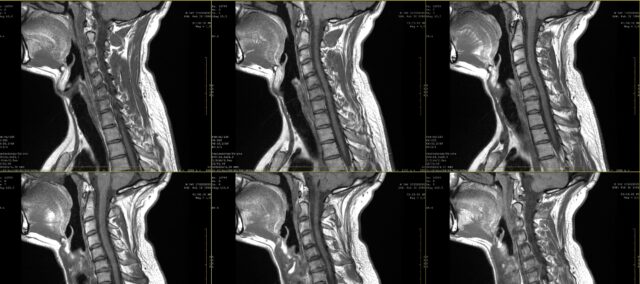

У школи сте сигурно учили о цртежима бола за радикуларни бол. Међутим, већ у првој деценији 21. века постало је јасно да радикуларни бол не мора да прати дерматомалну дистрибуцију. Ова студија је желела да ближе погледа договор између визуелне инспекције радикуларних цртежа бола како су приметили пацијенти и МРИ. У пракси, пацијент често изражава своје притужбе и то може бити допуњено цртежом бола. Када се сумња на радикуларни бол, често се прописује медицинско снимање како би се утврдио захваћени нервни корен и степен могућег захватања нервног корена. Иако ово у многим случајевима чини део рутинске праксе, не знамо док не сазнамо сагласност између ових цртежа бола и захваћеног нервног корена како је утврђено помоћу МРИ. У овој студији, Марцо ет ал. (2023) упоредили су цртеже радикуларног бола и налазе МРИ.

Да би се истражила сагласност између цртежа радикуларног бола и налаза магнетне резонанце, ова студија је укључила учеснике са 2-месечном историјом упорног бола, којима је дијагностикована цервикална радикулопатија на МРИ. Ову дијагнозу је поставио неурохирург на основу клиничких информација и налаза магнетне резонанце које је оценио радиолог.